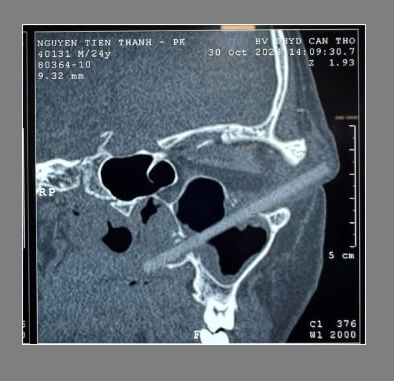

Неназванный мужчина был госпитализирован в Университет медицины и фармации Кантхо во вьетнамской провинции Кантхо, когда он пришел с симптомами боли и отека в левом глазу. 24-летний пациент сказал врачам, что он испытывает симптомы уже около трех недель, но в последние дни они ухудшились. Ранее он обращался за медицинской помощью в другое учреждение в своем родном городе, но после оценки его зрения и проверки на наличие инородных тел они прописали ему лекарство, которое оказалось неэффективным. Это привело мужчину в университетскую больницу Кантхо, где врачи еще раз подтвердили, что у него зрение 10/10, без признаков травмы глазного яблока. Однако левый глаз действительно выглядел опухшим, и из угла левого глаза было небольшое гнойное выделение. Последующее КТ показало, что в его глазнице застряло инородное тело длиной 9 см.

Быстрый осмотр показал, что таинственный объект, по-видимому, был деревянной палочкой для еды, которая проникла из мягких тканей за пределами левой глазницы, через верхнюю стенку верхнечелюстной пазухи и разрушила боковую носовую стенку. На вопрос, знает ли он, как палочка для еды могла застрять в его левом глазном яблоке, шокированный пациент смог вспомнить только «столкновение» с другом на пьяной вечеринке примерно в то время, когда у него начались боль и отек. Однако он не помнил явно, чтобы деревянная палочка для еды пронзила его пазухи или боль, связанную с таким жестоким инцидентом.